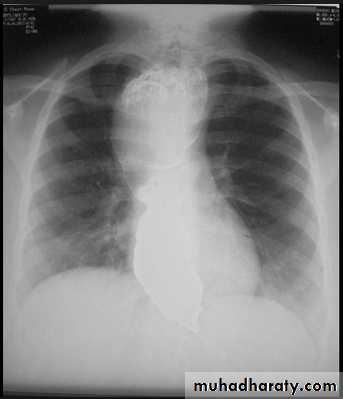

Massive pleural effusion with mediastinal shift to the left.

(A) Chest radiograph

(B) CT coronal reconstruction. A massive effusion displaces the mediastinum to the left. CT shows the important pleural effusion together with the enhanced atelectatic left lung.

Note also the depression of the right hemidiaphragm (arrows).